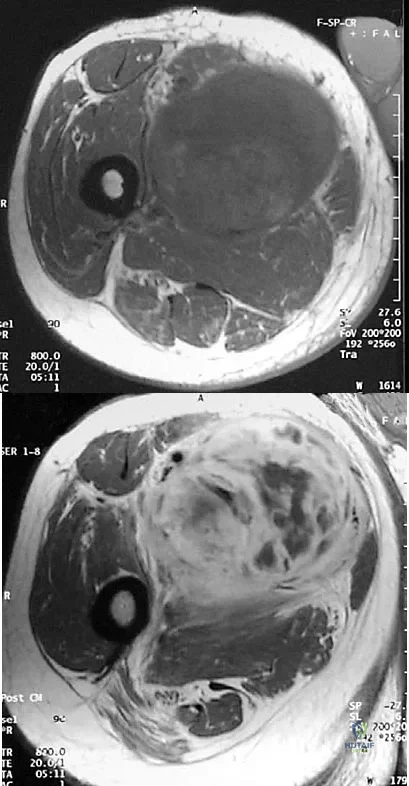

An athletic 55-year-old man reports a painless mass in the anterior aspect of the thigh that appeared 3 weeks ago and has not changed in size. The patient denies any history of trauma. Examination reveals a firm, well-defined nontender mass in the anterior thigh and no inguinal adenopathy or cutaneous changes. Plain radiographs are unremarkable. T1- and T2-weighted MRI scans are shown in Figures 44a and 44b. What is the most likely diagnosis?